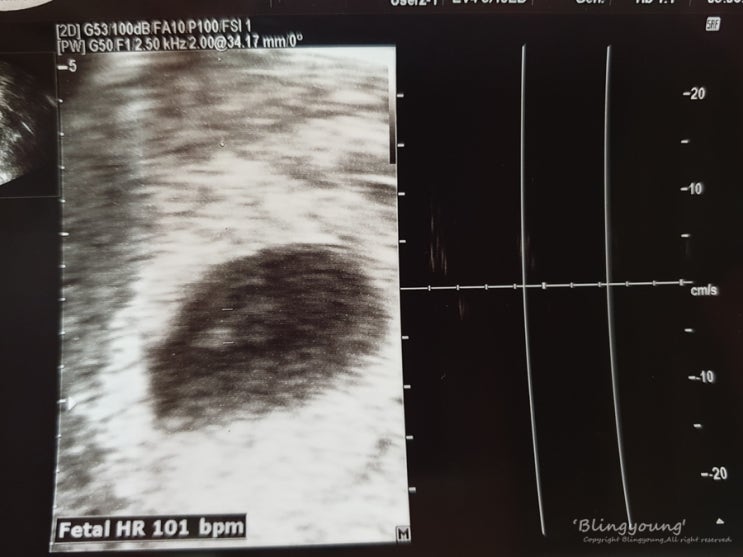

[임신기록] 땡큐 너를 확인하고 처음 만난 날, 임신확인서

[임신기록] 땡큐 너를 확인하고 처음 만난 날, 임신확인서 #임신테스트기 를 확인한 다음 날 정확한 임신 ...